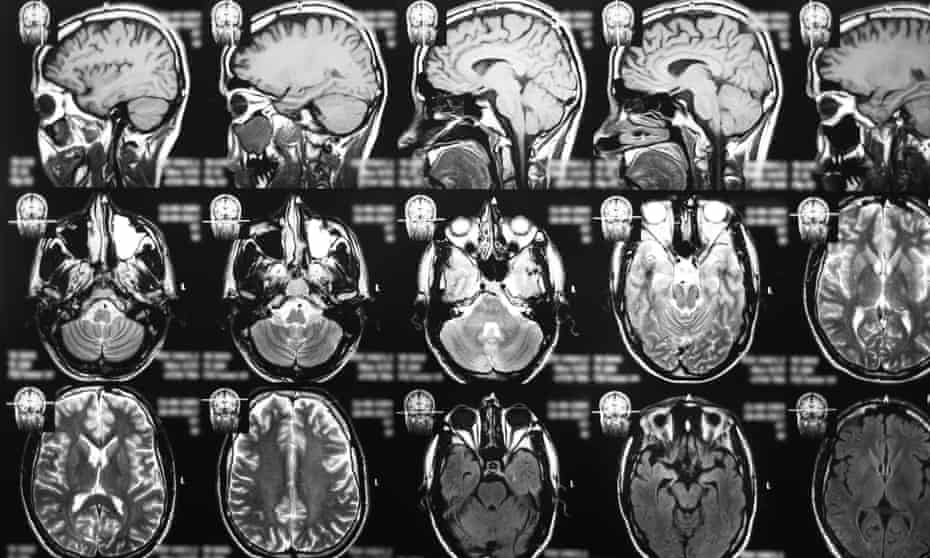

Early Findings Show New Drug Could Be Gamechanging For Brain Cancer Treatment Cancer Research The Guardian